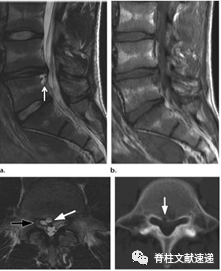

图注:背侧硬膜外椎间盘突出

图注:术前诊断倾向于硬膜外脓肿,术中见病灶呈致密纤维状,组织病理学检查显示纤维软骨盘伴反应性改变。

椎间盘背侧硬膜外突出移位是一种罕见现象。1973年,Lombardi首次将这种情况描述。

临床常与滑膜囊肿,脓肿,血肿或肿瘤相混淆。

马尾神经综合征在背侧硬膜外椎间盘突出中发生率更高(50%以上),神经根病也很常见。绝大多数发生位于腰椎区域,L3/4最常见,其次是L4/5。